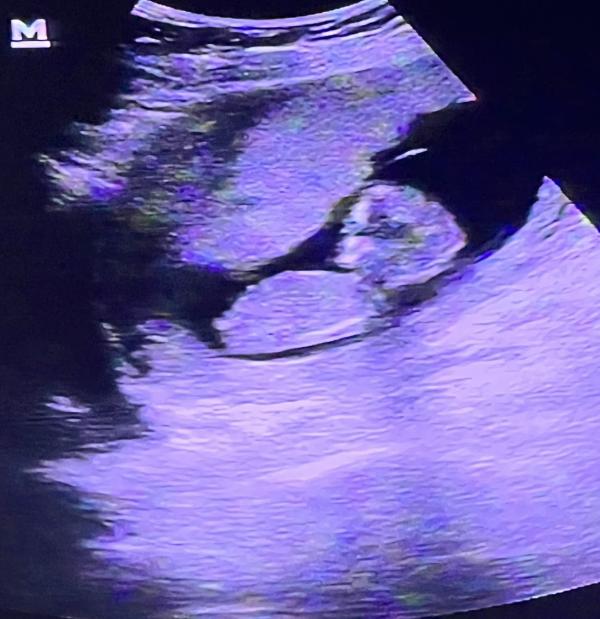

Сравнение животиков на 13 неделе беременности: первая и вторая

post image 2

милые моменты ❤️ на первом фото беременность сейчас, а на втором первая бер. оба в 13 недель ❤️

пол не видно сказали, но я хочу девочку 😂

У тебя девочка я тебе говорю , я вареник вижу там

а я яйца🤣